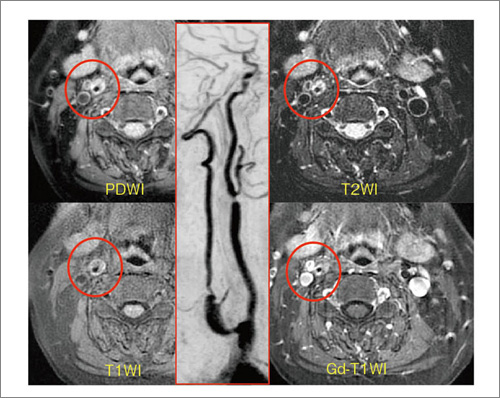

頸部Plaque Imaging

当院では,2009年1月から,“頸部Plaque Imaging”を開始した。撮像法を表1-(7)に示す。図11は総頸動脈を正面から見たMRAだが,欠損像が認められたため,Plaque Imagingを撮像した(図12)。図の○印内にある黒い部分が血管,周囲の白い部分がプラークである。どの撮像法でも,プラークが白く描出されている。

当院で頸部Plaque Imagingが開始されてまだ5か月であり,診断基準もまだ明確ではないが,血管内腔とプラークの両方が評価できるという意味では,非常に期待できると考えている。

図11 頸部MRA(総頸動脈)

図12 頸部Plaque Imaging